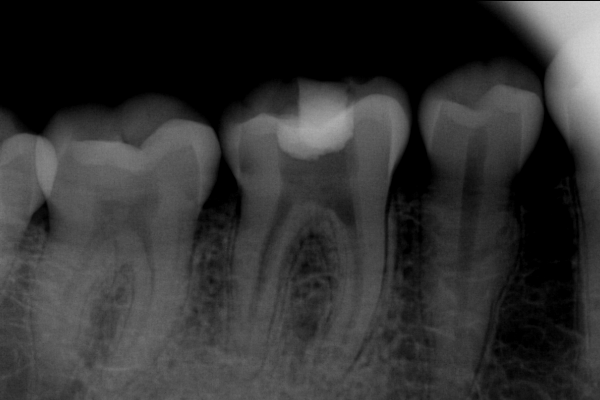

Paciente con infección de pulpa dental con dolor severo

Paciente masculino de 43 años de edad, con dolor severo y riesgo de pérdida de la pieza.

El paciente en su consulta de diagnóstico